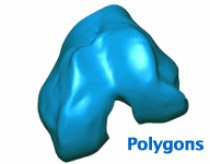

This is where 3D photography, the process of capturing a physical object and automatically processing it as an accurate digital model, comes in. Fregly’s team uses Geomagic Wrap software from 3D Systems to create detailed polygonal models from the point cloud data. These models use small triangles to create surface representations that are ideal for shape-related tasks such as image matching.

Fregly uses Geomagic Wrap’s curvature-based hole-filling to extrapolate missing surface data at the ends of the bones caused by the finite slice thickness that is inherent in medical imaging data. Next he uses a curvature-based decimation algorithm to reduce the number of polygons required to accurately represent each biological surface. The final decimated model can then be compared to the original point cloud data using Geomagic Wrap’s tolerance functionality to determine the accuracy of the polygonal surface fit.

Fregly also uses Geomagic Wrap to convert polygonal surface models, which are adequate for image matching, into the mathematical surface models necessary for contact stress analysis. Such models use a “quilt” of rectangular surface patches to create a mathematical representation of the geometry. Since the “seams” between the surface patches can complicate contact analyses, Fregly uses the software to merge all patches on a contact surface into a single patch. The same process is used to “resurface” CAD models of artificial knees for contact analysis. Any deviation between the polygonal model and the final mathematical surface representation can again be determined with Geomagic Wrap’s tolerance functionality.

Geomagic Wrap is used to create a detailed polygonal model from the point cloud data.

The polygonal surface deviates from the point cloud model by no more than 0.2 millimeters.